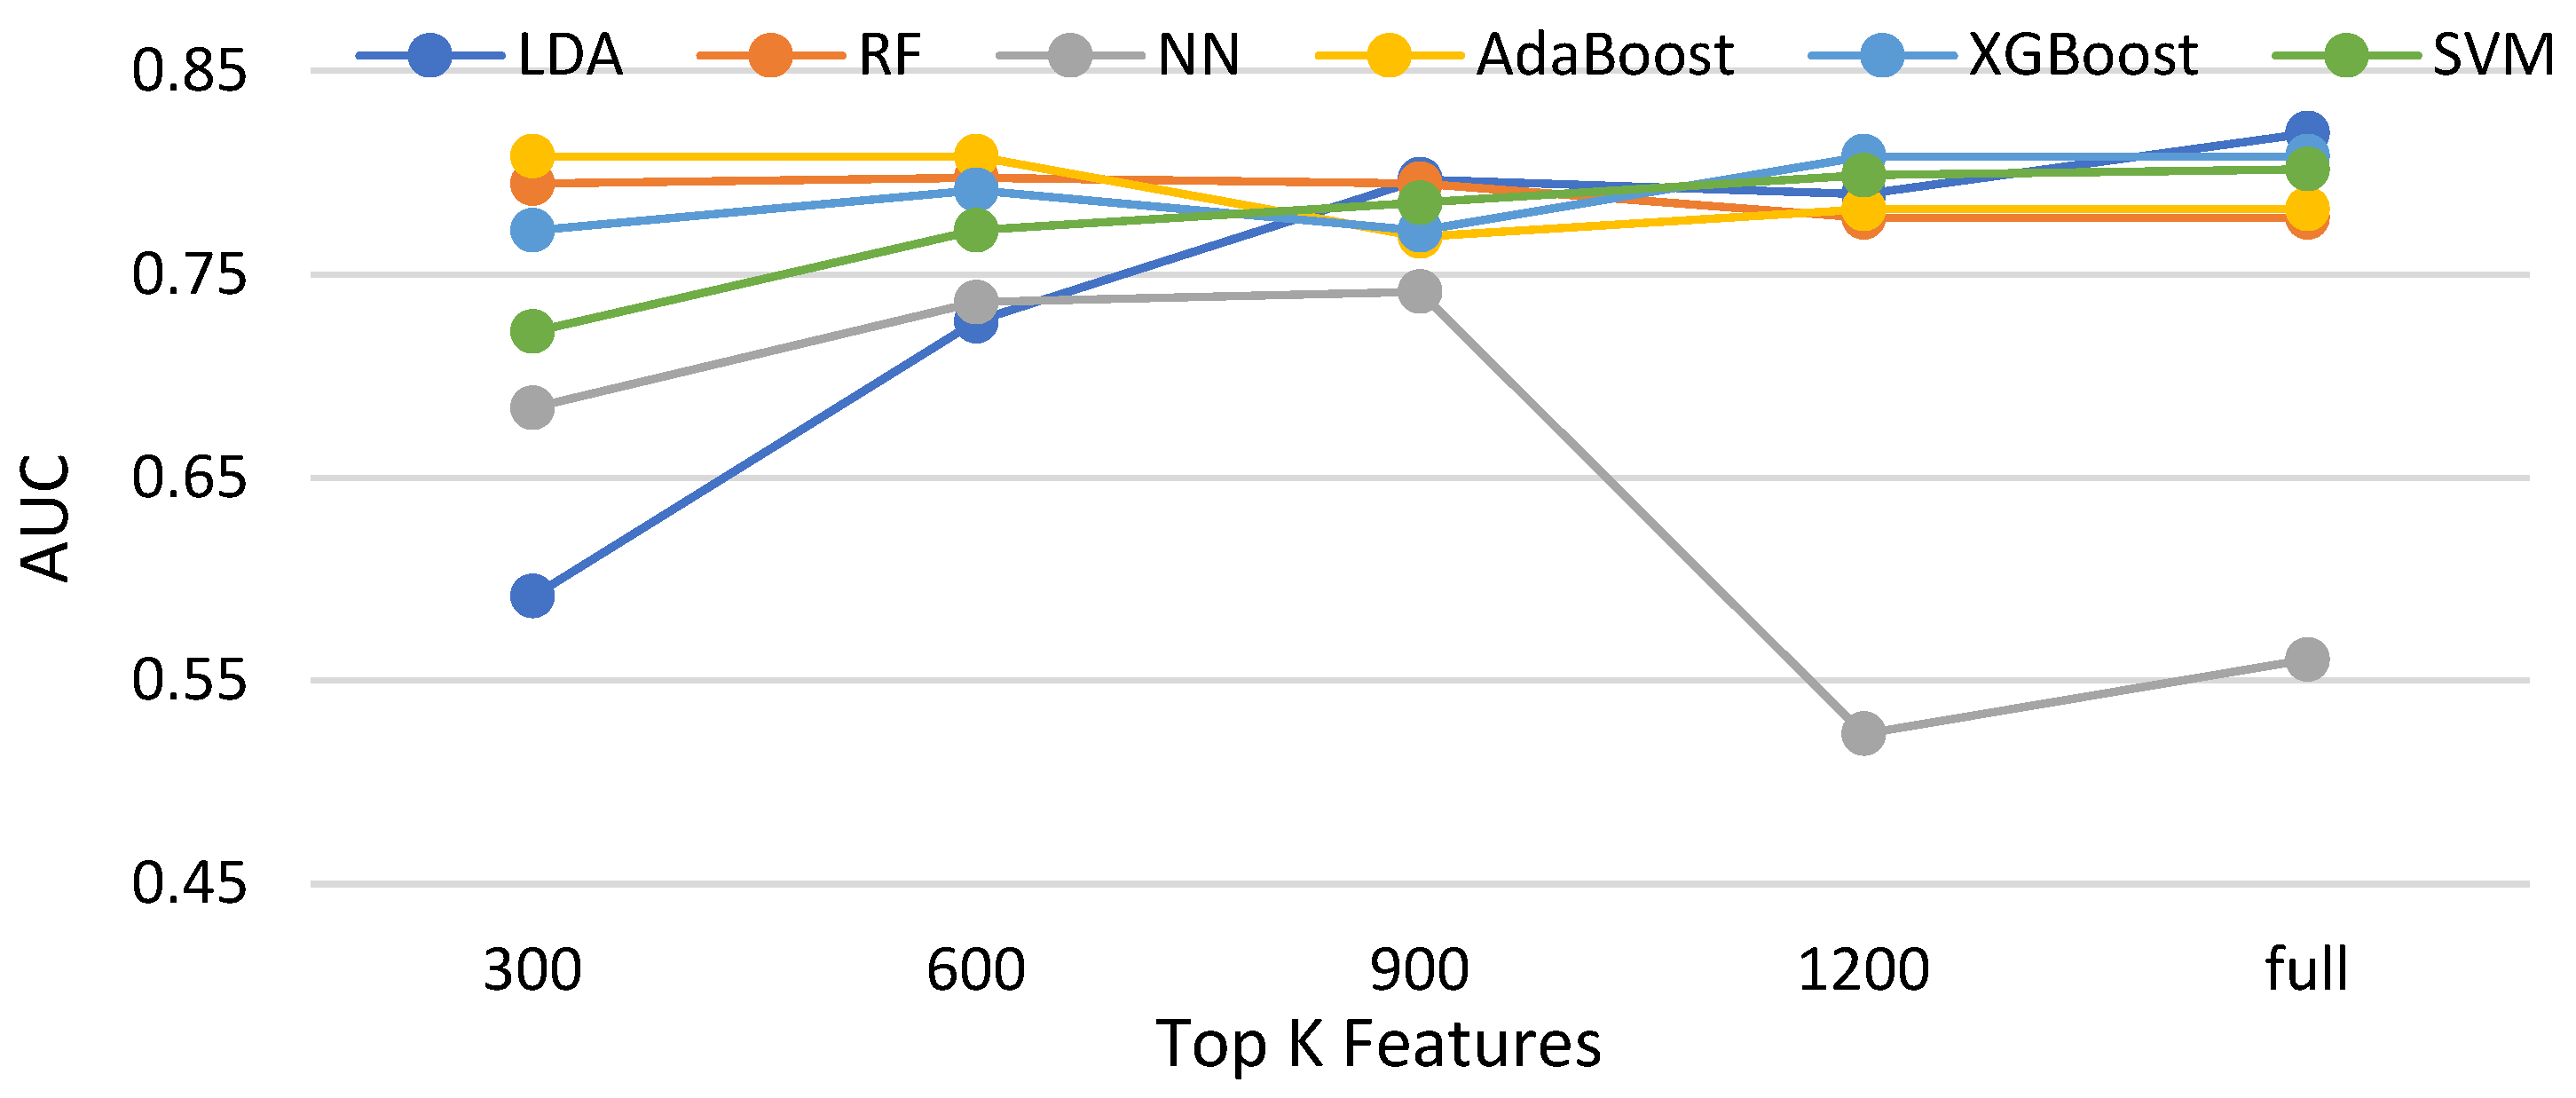

3.3.1. Effectiveness of Feature Selections for Compared Classifiers without Data Balancing